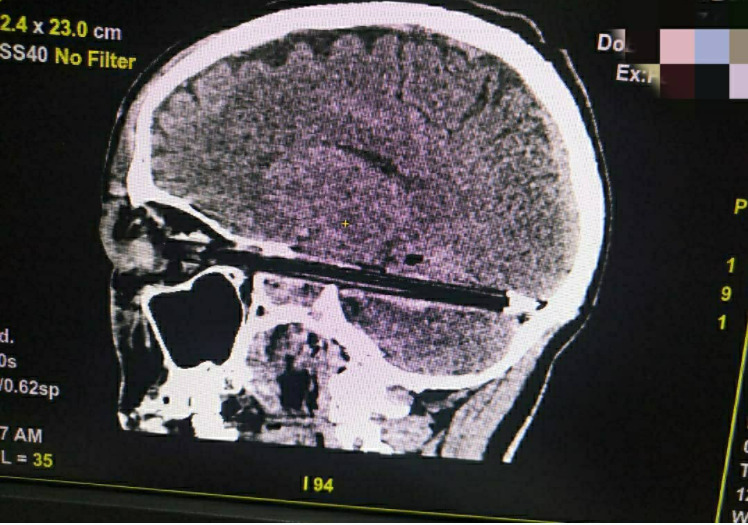

العثور على قلم في جمجمة رجل

منذ 4 سنة

4

3584